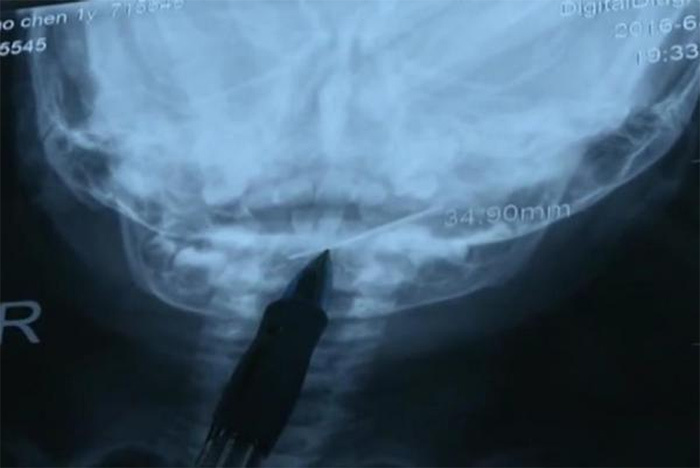

Cây kim dài 4cm được lôi ra khỏi họng bệnh nhân 1 tuổi. (Ảnh: NewsFlare) |

Video ghi lại ca phẫu thuật tại một bệnh viện ở Tây An thuộc tỉnh Thiểm Tây cho thấy, các bác sĩ nghiên cứu phim chụp tia X cổ họng của bệnh nhân nhí, với một cây kim hiện rất rõ.

Bé gái được cho là đã nuốt cây kim vào vài giờ trước khi được cha mẹ đưa tới bệnh viện.

Ca phẫu thuật diễn ra trong 30 giây. Bé gái được tin là sẽ phục hồi hoàn toàn.